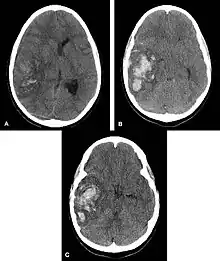

Multiple intraparenchymal hemorrhage

Intraparenchymal hemorrhage (IPH) is one form of intracerebral bleeding in which there is bleeding within brain parenchyma. The other form is intraventricular hemorrhage (IVH).[1]

Intraparenchymal hemorrhage accounts for approximately 8-13% of all strokes and results from a wide spectrum of disorders. It is more likely to result in death or major disability than ischemic stroke or subarachnoid hemorrhage, and therefore constitutes an immediate medical emergency. Intracerebral hemorrhages and accompanying edema may disrupt or compress adjacent brain tissue, leading to neurological dysfunction. Substantial displacement of brain parenchyma may cause elevation of intracranial pressure (ICP) and potentially fatal herniation syndromes.